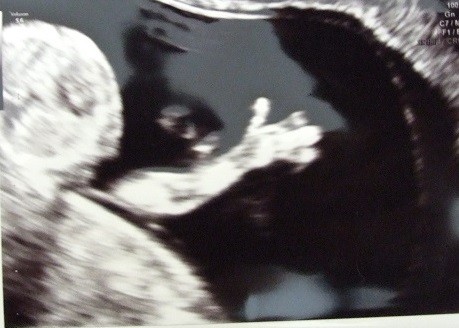

Lilunia ale słodko macha raczka [emoji8]

Lilunia uroczo macha lapka